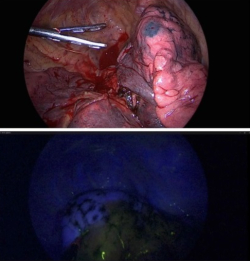

조현진 교수는 폐암 수술의 90% 이상을 흉강경을 이용한 최소 침습수술로 진행하고 수술 사망률이 0%로 수술 후 관리 측면에서도 우수한 결과를 나타내고 있다.

조현진 교수는 “폐의 바깥쪽 구역에 있는 1기 초기 폐암에서는 기존보다 폐 절제를 최소화하면서 근치적 절제를 할 수 있는 폐 구역 절제술이 앞으로 표준 수술이 될 가능성이 높다”며 “정확한 구역 절제를 위해 종양 위치 표시 및 형광 염료를 이용한 폐 구역 표시 기법이 최소 절제 수술에 도움을 줄 것”이라고 강조했다.